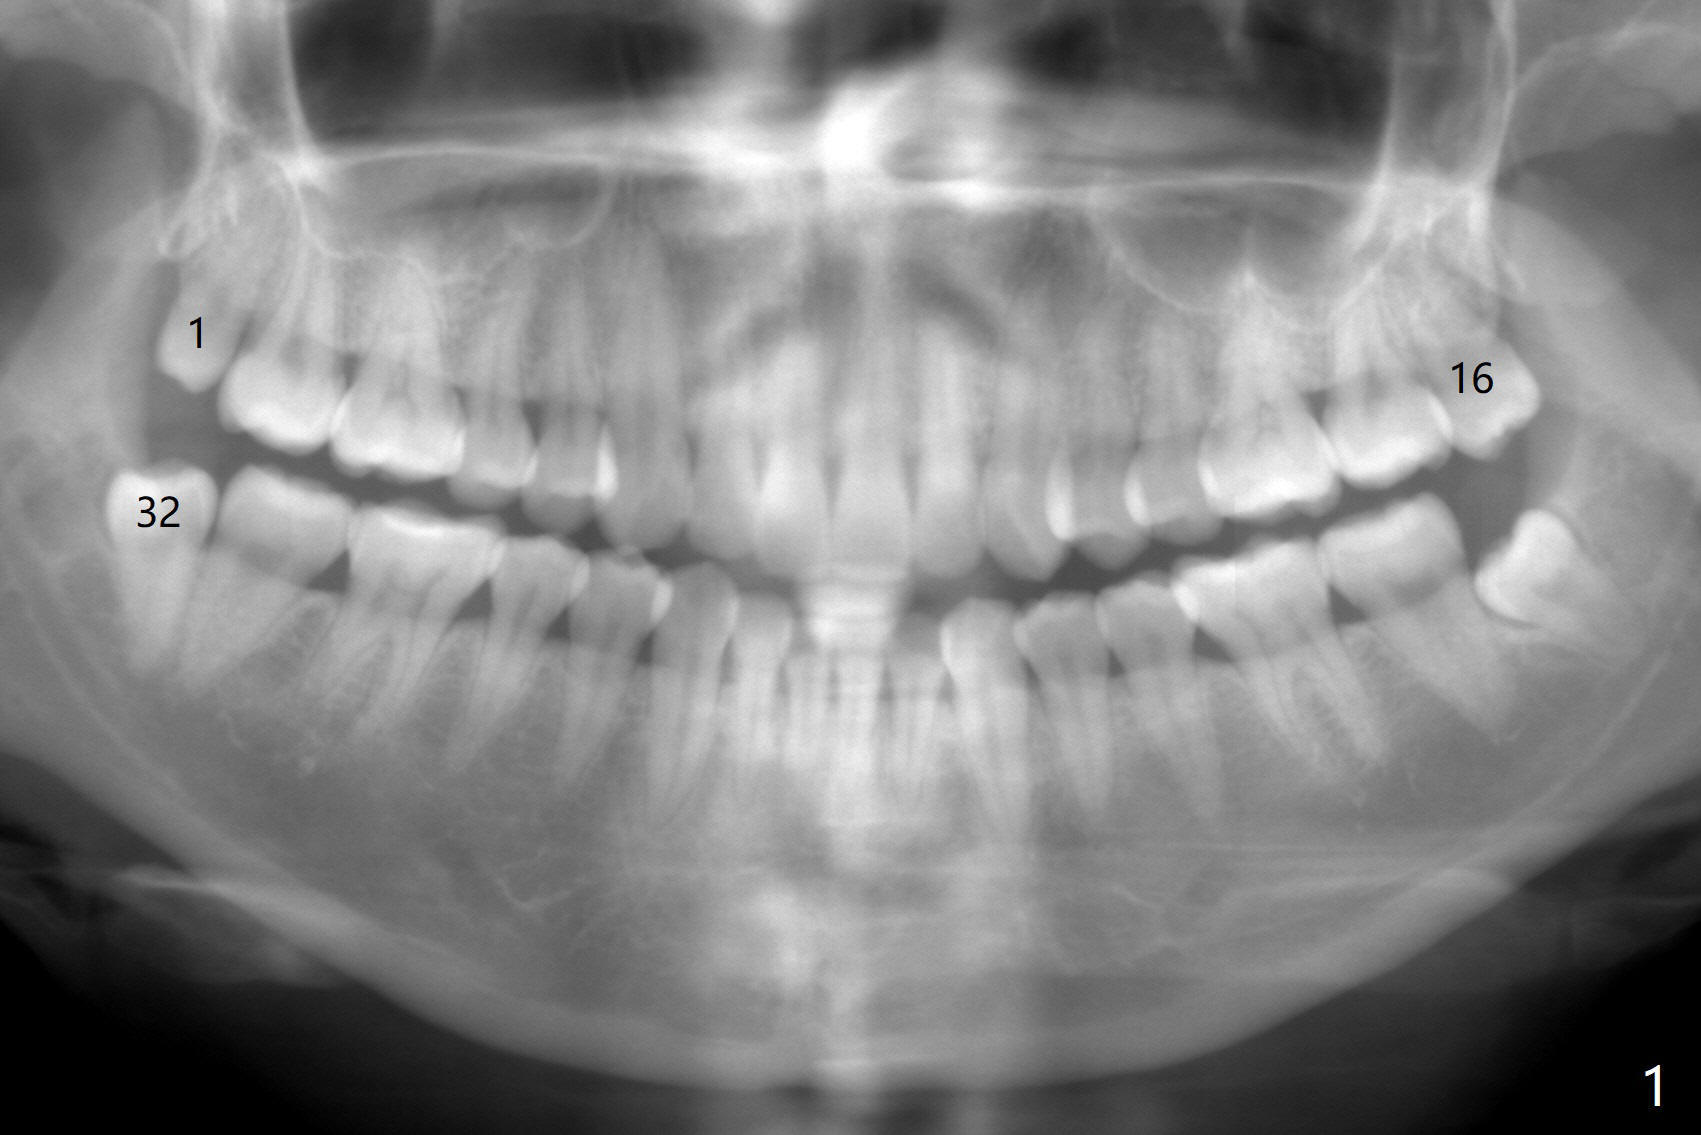

A 34-year-old lady requests extraction of #1, 16 and 32 (Fig.1). After incision for 32, surgical bur is used to create a purchase point to protect the thin bone between #31 and 32. The tooth is extracted with straight elevators and forceps. The socket is large single. Osteogen plug is placed with 4-0 plain gut suture (x4). There is cortical formation in the crest at #1, 16 and 32 three years postop (Fig.2-6 *, arrowheads). The advantage of Osteogen plug over Augma is easy placement with less risk of loss (by dissolving by saliva).